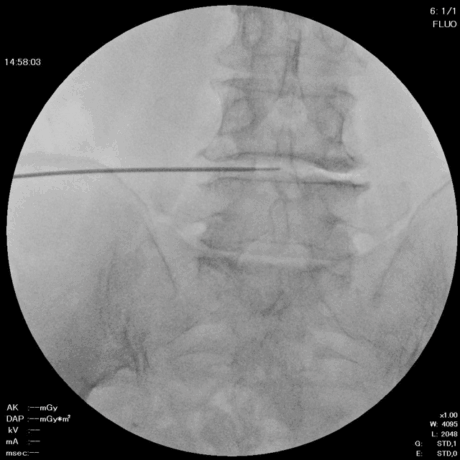

5. 線維輪の熱凝固(コアグレーション)

椎間板の線維輪に生じた亀裂部に対して、3〜6方向に5秒ずつ熱凝固を行います。

DISC-FX®:6方向 × 各6秒

DART:3方向 × 各6秒